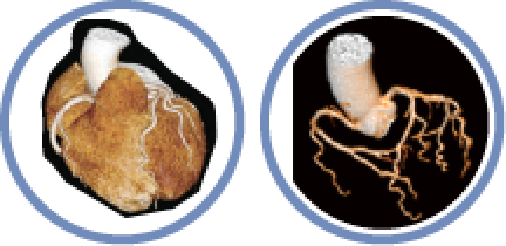

Precision in Cardiology

▪ Coronary Analysis

▪ Coronary Calcification Analysis

▪ Cardiac Function Analysis